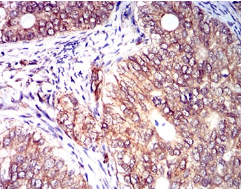

IHC    1/200 - 1/1000